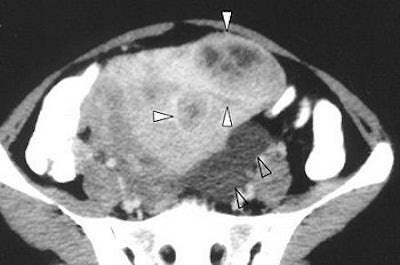

The CT exam with contrast showed heterogeneous enhancement of the solid components and septations of the corneal complex cystic lesions. T1- and T2-weighted MR scans showed isointense septations of the left cornual cystic lesions and small myometrial nodules. These same findings were hyperintense on gadolinium-enhanced MR.

In addition, uterine sarcoma has no specific features on CT to aid differential diagnosis. On MRI, it can be difficult to differentiate endometrial stromal sarcoma from leiomyosarcoma, which also has variable signal intensities on T2-weighted images.

| Axial T2-weighted MR image shows signal intensity of peritoneal inclusion cyst (solid arrowheads) appears to be brighter than that of ovarian cysts. Note left ovarian simple cyst and right ovarian follicle (open arrowheads). Toprak U, Pasaoglu E, Karademir MA, Gulbay M, "Sonographic, CT, and MRI Findings of Endometrial Stromal Sarcoma Located in the Myometrium and Associated with Peritoneal Inclusion Cyst," (AJR 2004 182; 1531-1533). |